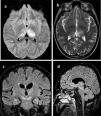

All patients underwent brain computed tomography (CT) evaluation, with no acute alterations being observed in any of them. In view of the presence of neurological clinical manifestations without CT abnormalities, brain magnetic resonance imaging (MRI) was requested in 6 patients, with the identification of structural lesions in three of them (Fig. 1).

Principales hallazgos en RMN en pacientes con infección por Virus del Nilo Occidental. Paciente 1: a) Cambios en la intensidad de señal en el margen posterior de ambos tálamos, fundamentalmente el izquierdo con hipointensidad heterogénea en T1. b) hiperintensidad heterogénea en secuencia T2 en ambos tálamos principalmente izquierdo. Paciente 2: c) alteración del tronco del encéfalo con afectación hiperintensa marcada en banda en ambos pedúnculos cerebrales del mesencéfalo. Paciente 3: d) Lesión hiperintensa en la línea media del mesencéfalo que se extiende caudal hasta la protuberancia.